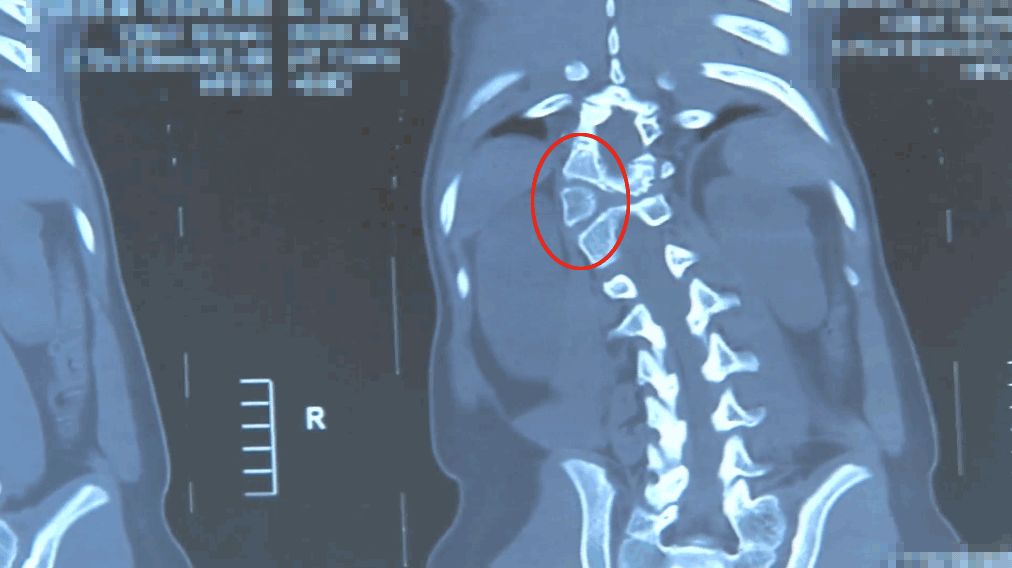

脊柱側彎,即脊柱向側方彎曲——正常人的脊柱從正面看是直的,而脊柱側彎患者的脊柱從正面看是呈字母「C」形或者「S」形的。

由于人體的脊柱是三維結構,從三維上看,脊柱側彎會伴有脊柱結構的旋轉,是一種三維的脊柱畸形。

半椎體切除術,是目前治療半椎體畸形最理想的方法。